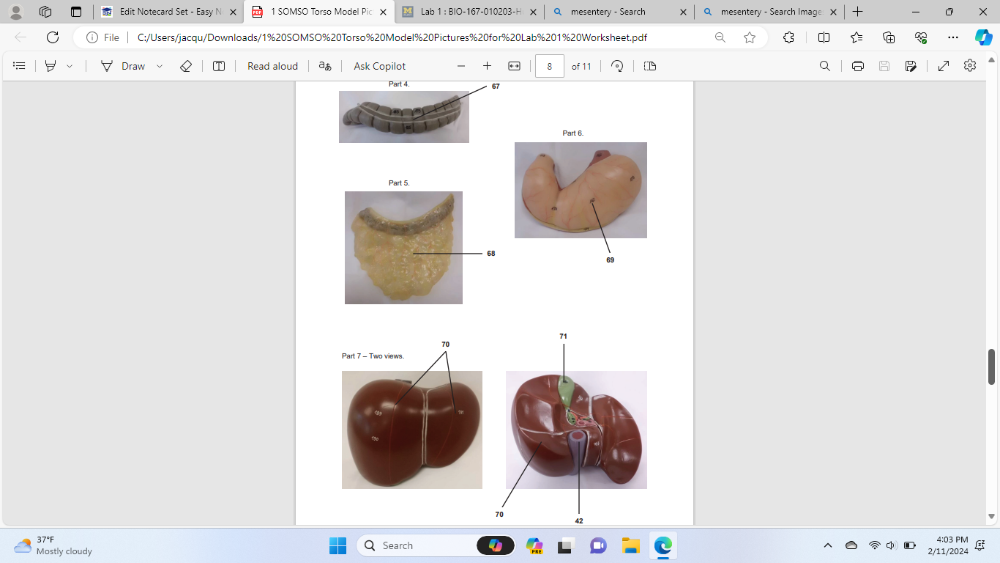

transverse colon

Identify the specific organ/structure labeled 68

greater omentum

Identify the specific organ labeled 69

stomach

Identify the specific organ labeled 70

liver

Identify the specific organ labeled 71

gallbladder

Identify the specific organ labeled 42

inferior vena cava

Identify the specific organ and side labeled 31

left long

Identify the specific muscle labeled 34

Diaphragm

Identify the specific organ and side labeled 35

Right lung

Identify the specific blood vessel labeled 37

superior vena cava